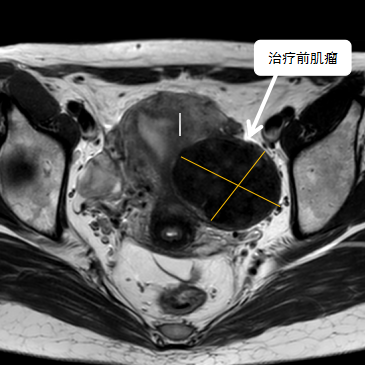

術(shù)前影像資料

經(jīng)過兩個月的藥物預(yù)處理,完善術(shù)前準備,治療當(dāng)天陳主任帶領(lǐng)團隊在3.0T磁共振清晰圖像引導(dǎo)下對子宮肌瘤進行精準消融,患者全程清醒,沒有明顯疼痛,經(jīng)過1個多小時的精細操作,手術(shù)非常成功,消融率接近90%,內(nèi)膜未見損傷!觀察一個小時后患者即自行回家。

術(shù)后即刻行增強磁共振檢查,顯示病變被消融近90%,內(nèi)膜未見損傷